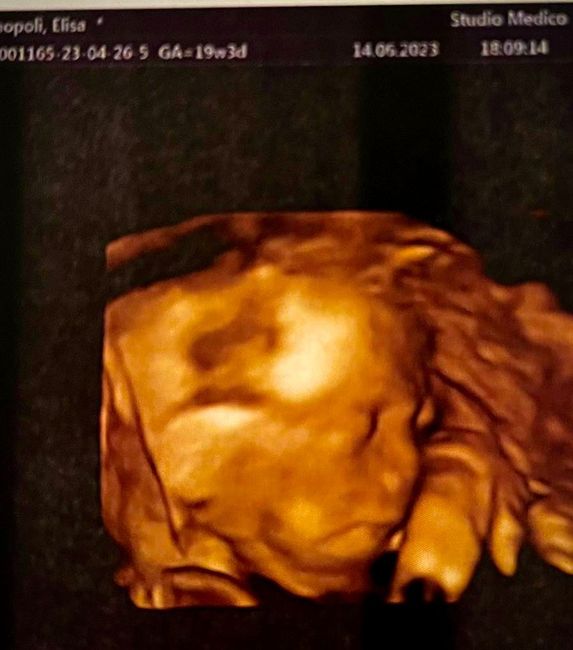

Da Elisa , Il 15 Giugno 2023 alle 09:12

Ciao a tutte!ecco il gruppo per farci compagnia in questi mesi di attesa! Di seguito lascio la lista ( in continuo aggiornamento per chi vuole essere aggiunta, per chi...